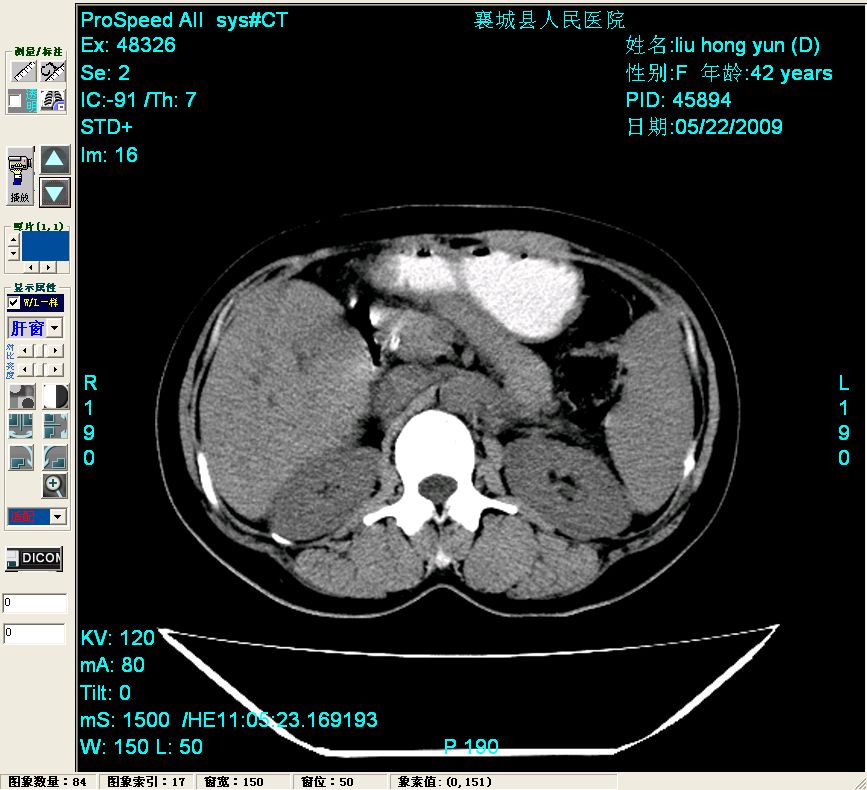

平扫:

平扫左肝外叶体积显著减小,左肝外叶见多房囊性低密度区,左肝实质及右肝前叶浅表实质呈低密度改变,左肝及右肝前叶胆管扩张,脾大

胰头部见结节状高密度影,其前方略可分辨扩强胆部管,平扫到增强始终有,但现在尚难与胃肠造影剂鉴别.

结合病史考虑,1现在引起黄疸体征的原因应该是胆总管胰段结石阻塞,建议局部胃肠造影剂排空后复查.

考虑:1、胆道结石伴肝内胆管扩张、积气;胆系感染!2、从平扫、增强片来看,不存在胆管肿瘤征象;3、提介建议:作为影像医师,在做一项检查之前应先熟悉临床医生的目的,象这个病例,检查前就不应喝高密度造影剂,而应充分喝好水就可,要不适得其反,反而较难判断胆总管下段是否有结石。